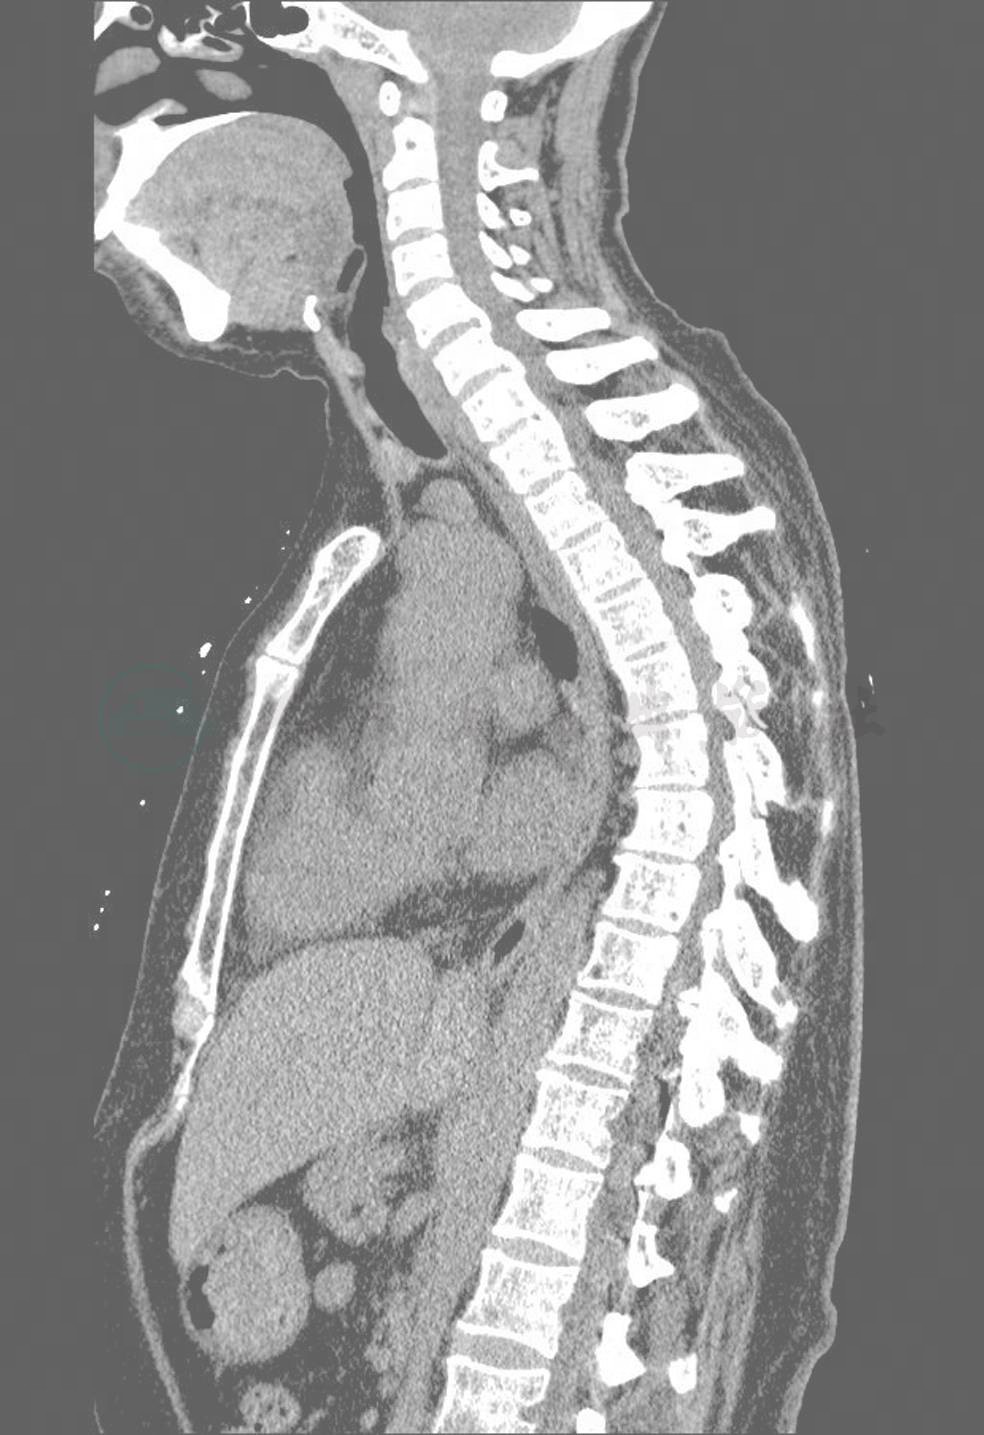

术前CT:胸椎向右侧弯,伴后凸(图3)。C5-T1后纵韧带骨化,相应节段骨性椎管前后径变窄(图3),最窄处约7.5mm。T1左侧黄韧带及T3-11双侧黄韧带肥厚骨化,胸段骨性椎管不同程度狭窄(图4),最窄处约8mm。颈胸椎体及胸椎小关节可见骨质增生,椎小关节间隙变窄。C4-T5椎间盘向后突出,相应水平硬膜囊前缘稍受压改变。

图3 术前CT可见C5-T1后纵韧带骨化明显,胸椎后凸